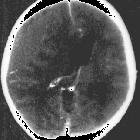

In almost all cases, extradural hematomas are seen on CT scans of the brain. They are typically bi-convex (or lentiform) in shape, and most frequently beneath the squamous part of the temporal bone. EDHs are hyperdense, somewhat heterogeneous, and sharply demarcated. Depending on their size, secondary features of mass effect (e.g. midline shift, subfalcine herniation, uncal herniation) may be present.

When acute bleeding is occurring at the time of CT scanning the non-clotted fresh blood is typically less hyperdense, and a swirl sign may be evident .

Postcontrast extravasation may be seen rarely in case of acute EDH and peripheral enhancement due to granulation and neovascularization can be seen in chronic EDH.